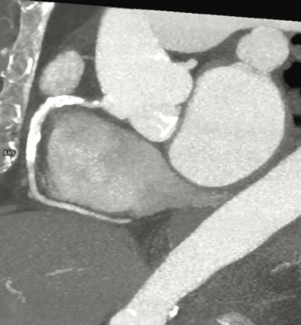

Constrictive pericarditis is a morbid condition, with a challenging diagnosis. Because constrictive pericarditis is generally considered a treatable cause of heart failure, evaluating for and distinguishing constrictive pericarditis from...

In this issue of CLD, Manjunath et al present a case of a woman who presented with heart failure due to constrictive pericarditis. She had been treated with chemotherapy and chest radiation therapy for Hodgkin’s lymphoma.